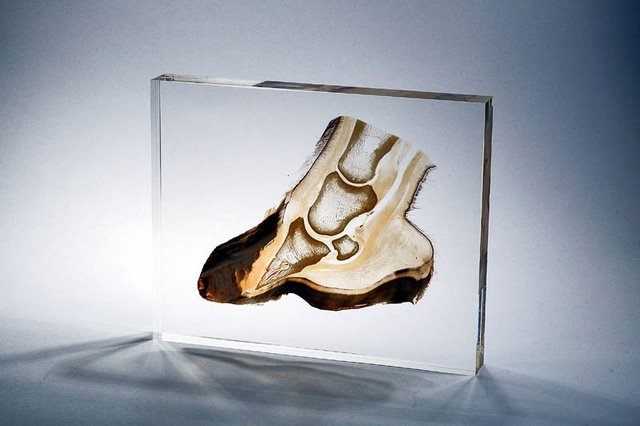

Omstreeks 1895 publiceerde Wilhelm Röntgen de eerste artikelen betreffende zijn ontdekkingen van ‘de nieuwe straling’. Röntgen zelf noemde deze straling de ‘X-straling’, naar de onbekende variabele in de wiskunde. De straling wordt (meestal) opgewekt in een röntgenbuis. Met de juiste energie zal de straling voor beeldvorming kunnen zorgen. Dit komt doordat de straling door de meeste zachte weefsels heen gaat, maar door harder weefsel wordt tegengehouden. Zo houdt het bot bijvoorbeeld veel straling tegen. Het kraakbeen is zachter en houdt zodoende veel minder tot geen straling tegen. Hierdoor zijn de botten duidelijk te zien op het beeld. Met röntgenstraling kan dus het skelet van mens en dier worden afgebeeld.

Bij een paard dat hoefbevangen is, zal er een röntgenfoto gemaakt moeten worden om vast te kunnen stellen in welke fase de hoefbevangenheid is. Op de beelden is dan precies te zien welke vorm van hoefbevangenheid het paard heeft, hoe ernstig de situatie is en of er sprake is van bijvoorbeeld kanteling of verzakking van het hoefbeen.